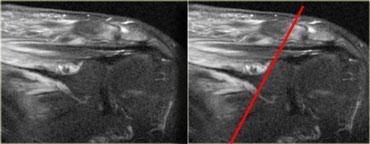

Tiền sử bệnh thường là chìa khóa chẩn đoán, nhưng ngoài ra có thể thấy hình ảnh dạng dải nơi các thay đổi do xạ trị trong cơ dừng lại, tương ứng với trường chiếu xạ.